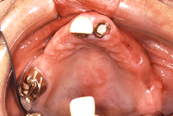

インプラント埋入後

上顎に2本、下顎4本インプラント埋入

磁性アタッチメント(磁石)使用

どんなお悩み | 他院で入れ歯を製作したが入れていなくて、長く放置され歯周病がすすみ歯がグラグラになって来院した患者さん。上顎のグラグラの歯を3本抜いて、そして上顎2本、下顎4本インプラントを埋入し 上顎がコーヌスクローネ義歯、上顎・下顎ともにインプラント部に磁性アタッチメント(磁石)使用。 |